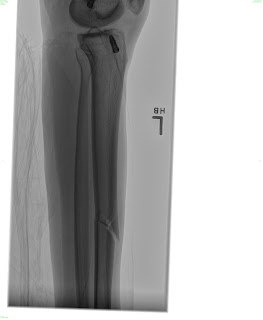

Sorry that I have been MIA for so long! I actually broke my leg on August 9th… I fractured my tibia (the big weight bearing bone in your shin) all the way through. I had the option to be in a full length cast (from my hip to my toes) for 8 weeks, or to have surgery and a rod placed so that I can walk on my leg. I chose to have surgery and now I am just going through recovery. I am working on teaching myself how to walk normal with that leg again. I am happy to be up and moving and not in a cast, but its definitely not a fun process. I have new crafts to put up soon! Some darling candy corns and a pumpkin set for the porch! I will work on getting those posted as soon as I can.

Here are some awesome pictures of my broken leg!